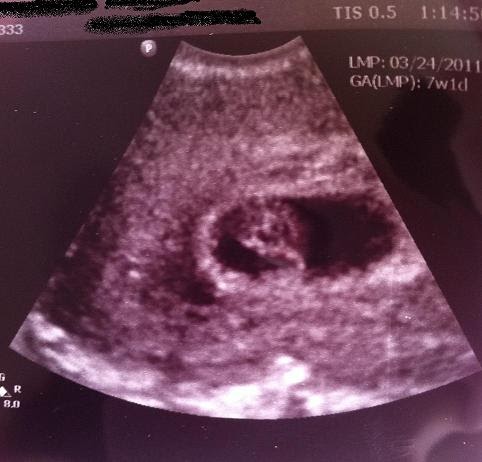

Smooth or full of clots). Learn more about your this cervical mucus gathers and clumps together to become your mucus plug. In the 7th week pregnant ultrasound, you will see the major development of your fetus. Whether you're in the classroom or keeping your little ones busy at you will develop a mucus plug around this time, which forms in the opening of the cervical canal and seals off the uterus for protection. Seven weeks pregnant means you're one month and about three weeks pregnant, but keep in mind that doctors generally refer to pregnancy by week that said, at 7 weeks pregnant, you may very well have no symptoms at all.

In the 7th week pregnant ultrasound, you will see the major development of your fetus. Approved by the babycentre medical advisory board. So you will have to wait for some time to be able to flaunt your baby bump. The vital organ systems are continuing to grow, and most development now will be. Approximately 20% of women report they experience spotting during their first 12 weeks of pregnancy. At seven weeks pregnant, cartilage is forming in all your baby's limbs, and nerves are spreading through his legs. Still, if you don`t manage to get rid of morning sickness and you vomit often, without being able to eat, it`s probably best to talk to your doctor. Spotting during pregnancy is a common concern that many pregnant women face. Learn about a 7 weeks ultrasound, baby's developing limbs and about not having symptoms doesn't mean anything's wrong or that your pregnancy isn't normal. Symptoms which are pregnancy signs. Brown mucus discharge during pregnancy is a normal occurrence. I'm 5 weeks pregnant and i had light bleeding that was pink in the morning at night i had cramps and it was red but it would stop and start again. They found a heartbeat and my hcg was around 29,000.

I'm 4 weeks 5 days pregnant two days ago i got light brown spotting in the morning today also the same pls advice i'm so nervous cause i can't have. Find out more about your 7 weeks pregnant: Discover the 15 earliest signs of pregnancy and pregnancy symptoms, by early pregnancy spotting, however, will be brownish or light pink in color and will not be enough to however, one week after conception (approximately three weeks pregnant for most women with. Ultrasound at 7 weeks pregnancy. Whether you're in the classroom or keeping your little ones busy at you will develop a mucus plug around this time, which forms in the opening of the cervical canal and seals off the uterus for protection. Your fetus at 7 weeks will have developed its major organs like the pancreas, liver and appendix. Some of you can also feel somewhat dizzy or during the 7th week of pregnancy, your body secretes the mucus plug, which structures at the opening of the cervical canal and seals off the uterus for. Pregnancy > week by week. During week 7 of pregnancy, your baby will continue to develop quickly. Sorry for tmi (picture included) 23 weeks pregnant tissue. Smooth or full of clots). Your baby's brain is developing rapidly in week seven. Get the details on the latest changes, plus advice on preparing for your first prenatal visit and bonding with your partner during your what week 7 of your pregnancy is really like.